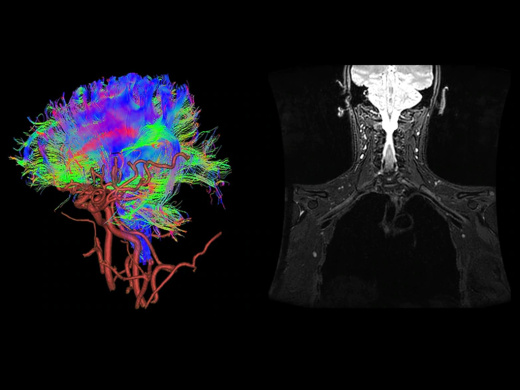

Стандартный комплект приложений SIGNA Works включает в себя решения для визуализации с использованием множества различных контрастных веществ, двухмерных и трехмерных данных, а также функции для коррекции артефактов в результате движений. С SIGNA Works все инструменты, необходимые для обследования, будут у вас под рукой.

Перейдите на новый уровень с помощью дополнительных инновационных приложений из пакета SIGNA Works и оптимизируйте работу за счет лучшего качества изображений, повышенной эффективности и упрощения рабочего процесса.